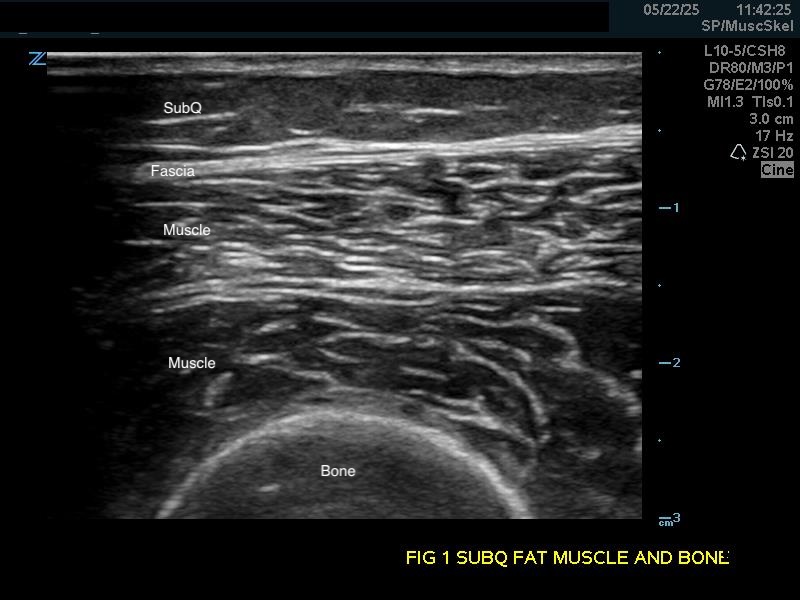

Bones

Bright hyperechoic lines with no echoes deep to the densely calcified cortex. Ultrasound can only view the surface of bones.

Figure 1a.

(A) Longitudinal view. Bone appears as a distinct bright echogenic line with no visible structures beneath, Subcutaneous fat appears relatively hypoechoic with thin septations of connective tissue.

Soft Tissue

Subcutaneous fat: Relatively hypoechoic with thin septations of connective tissue. The thickness of this layer varies and may require increasing the depth setting of your machine.

Muscle: Longitudinally, appears as slabs of striated hypoechoic tissue contained within the thin hyperechoic lines of fascia. Viewed transversely, muscle striations or septa appear dotted and punctate or form short lines. Fascial lines separate muscle compartments.